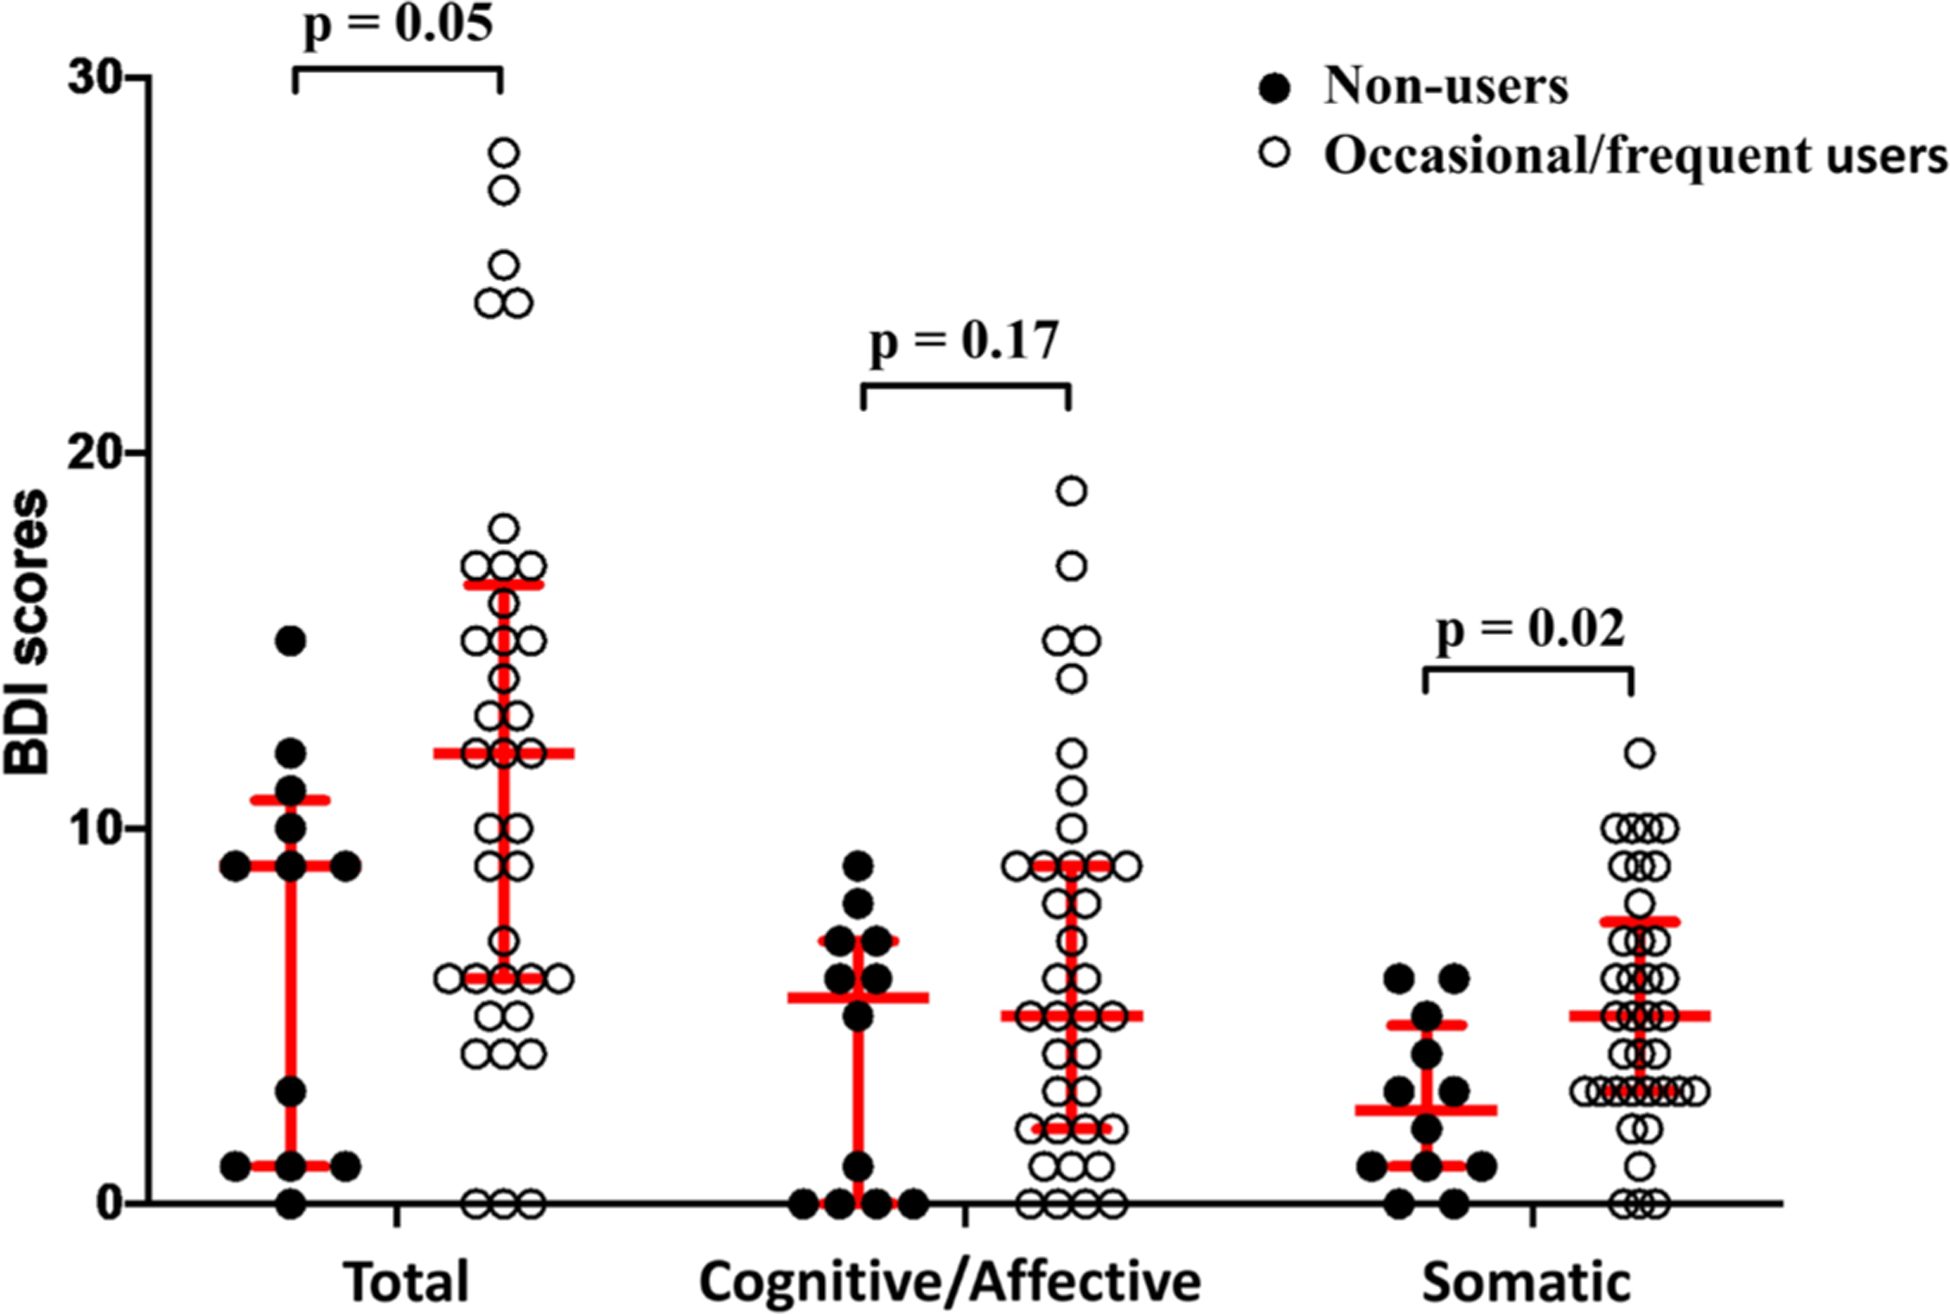

Occasional/frequent use was associated with more somatic symptoms in HIV+ participants (Figure 3). Median (Q1 – Q3) BDI-somatic scores were 5.0 (3.0 – 7.0) for occasional/frequent users vs. 2.5 (1.0 – 4.75) for non-users (p = 0.016). Cognitive/affective BDI scores did not differ between occasional/frequent (5.0 [2.0 – 9.0]) and non-users (5.5 [0 – 7.0]; p = 0.17), but occasional/frequent users showed a trend toward higher total BDI (12.0 [6.0 – 16.5] vs. 9.0 [1.0 – 10.75]; p = 0.052). A trend association existed between higher BDI-somatic scores and recent vs. remote use (6.0 [3.0 – 9.0] vs. 3.0 [2.0 – 6.0]; p = 0.063). HIV− individuals exhibited no relationships between cannabis use and BDI.